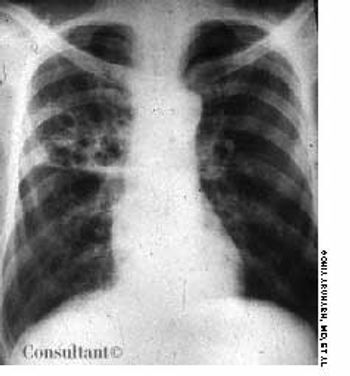

An 85-year-old man was admitted to the hospital with a cough and shortness of breath of 1 week's duration and a fever and increased sputum production for 2 days. His history included renal cell carcinoma and metastatic renal cancer for 2 years. The patient had smoked cigarettes for 30 years. He had lost 30 lb during the last few months.